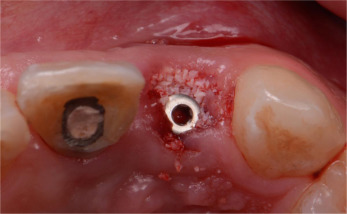

Fig. 6

Fig. 6.

(a) Implant (3.5 mm×15 mm) placed at extracted socket of central incisor. (b) Implant (3 mm×15 mm) placed at extracted socket of lateral incisor.